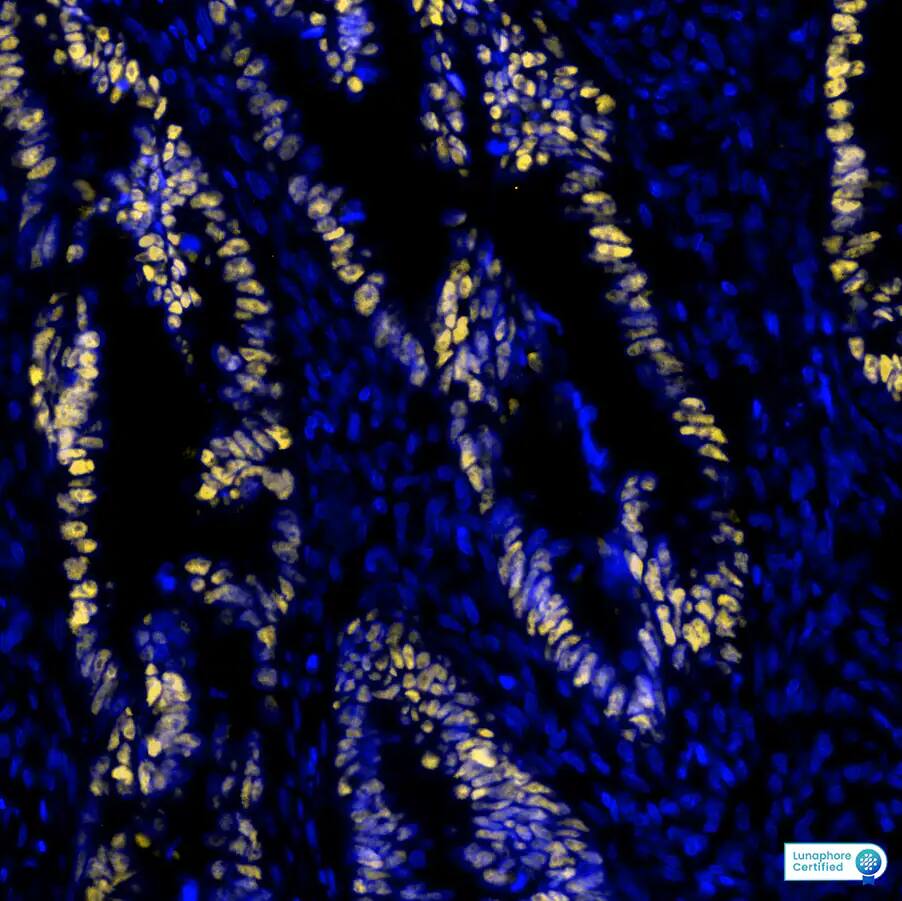

p53 was detected in immersion fixed paraffin-embedded sections of human Colon Tumor using Mouse Anti-Human p53 Monoclonal Antibody at 12ug/mL at 37°Celsius for 8 minutes. Before incubation with the primary antibody, ...read more

Immunohistochemistry-Paraffin: p53 Antibody (BP53-12) - IHC-Prediluted [NBP2-44976] - Formalin-paraffin human colon carcinoma stained with p53 Ab (BP53-12).